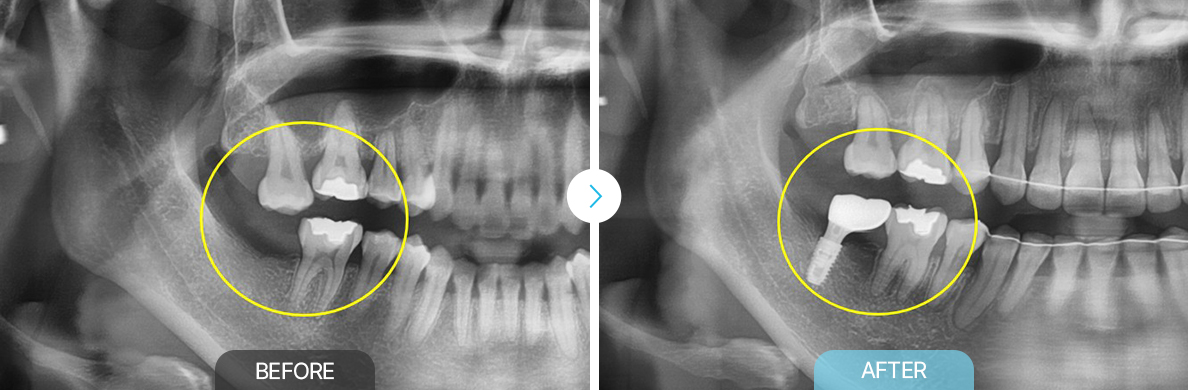

치료전후사진

보철교정

부천상동 보철교정, 상동 보철교정, 부천치과 부천연세퍼스트치과 보철교정, 부천상동 교정, 보철교정 상동